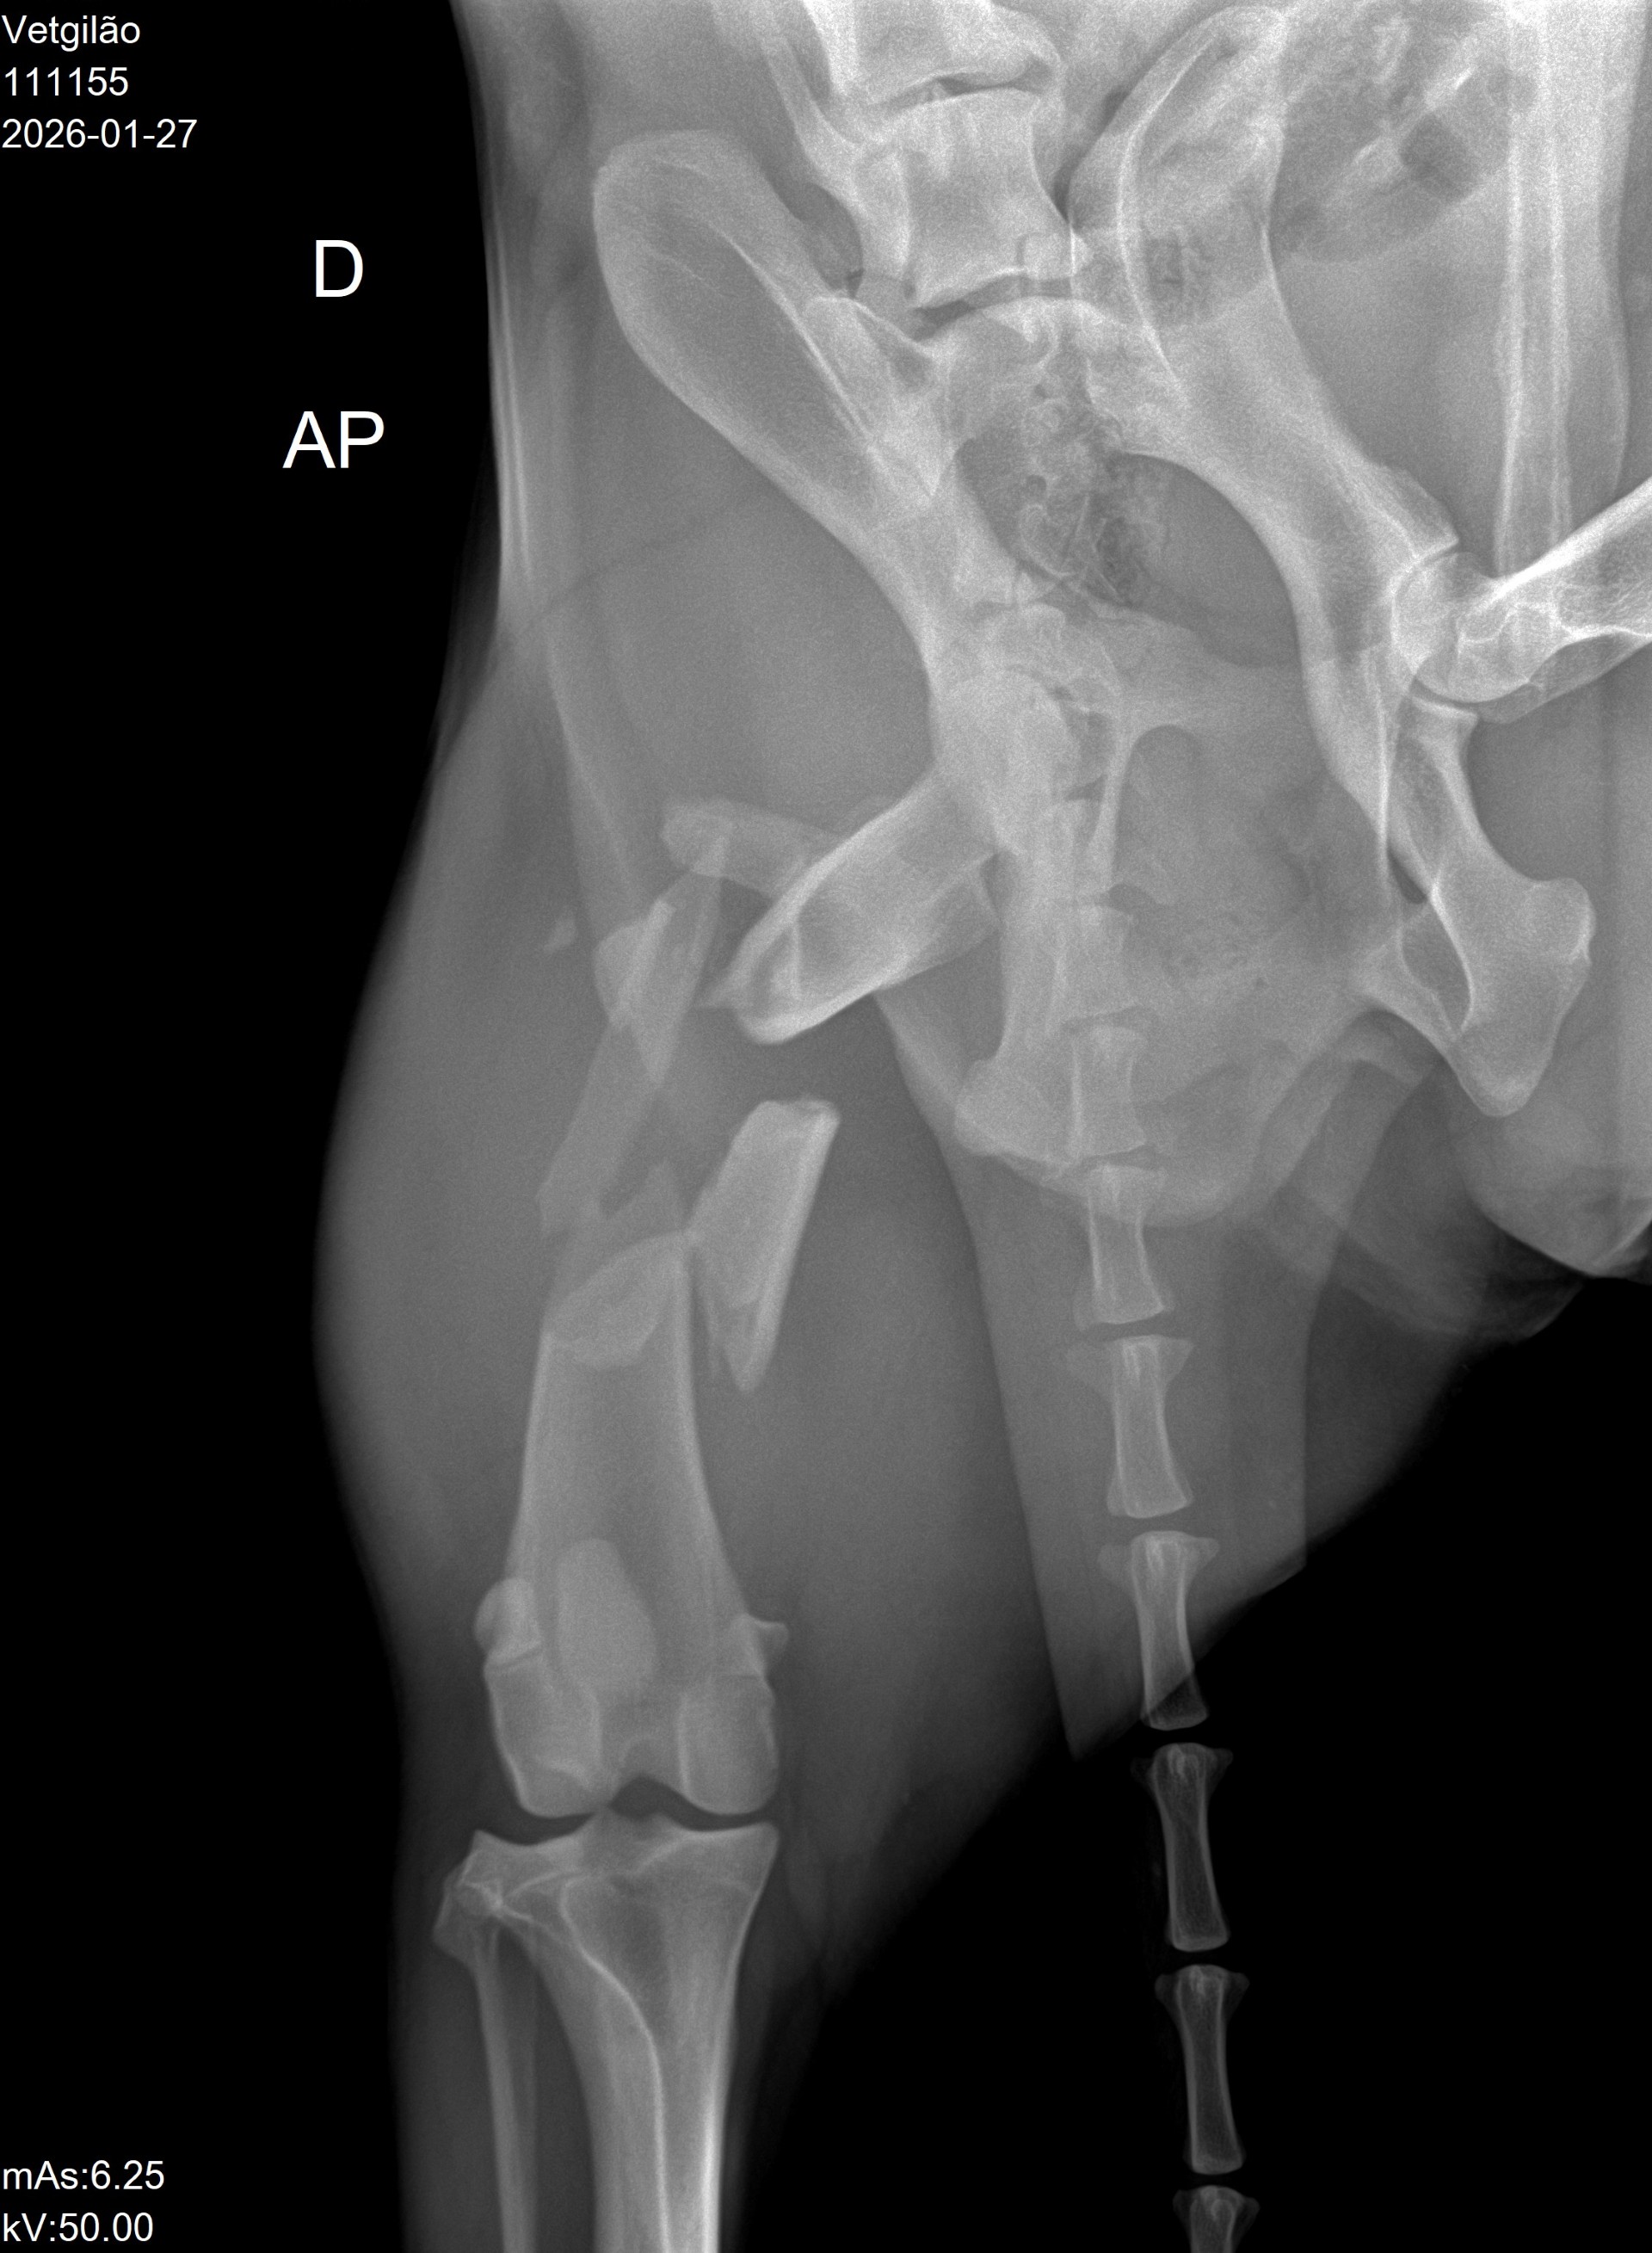

Um lindo Pastor Alemão chamado Max partiu a pata traseira em vários sítios, e a operação para a reparar custaria 1400 euros. O veterinário pediu-nos ajuda, pois o dono não conseguia pagar. Pagámos 700 euros pela operação, e esperamos que fique como novo.

Max

Raio-X do Max